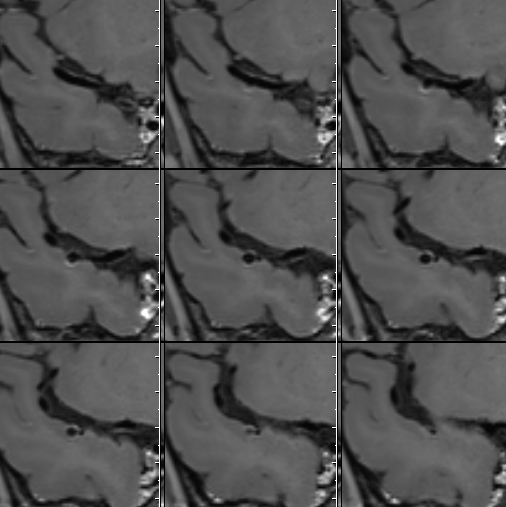

HRMRI

左侧脑室旁亚急性期-慢性期脑梗死

右侧大脑中动脉瘤,右侧椎动脉V2-V3粗细不均伴局部扩张

右侧大脑中动脉瘤,瘤壁强化

右侧椎动脉局部梭形扩张,管壁增厚